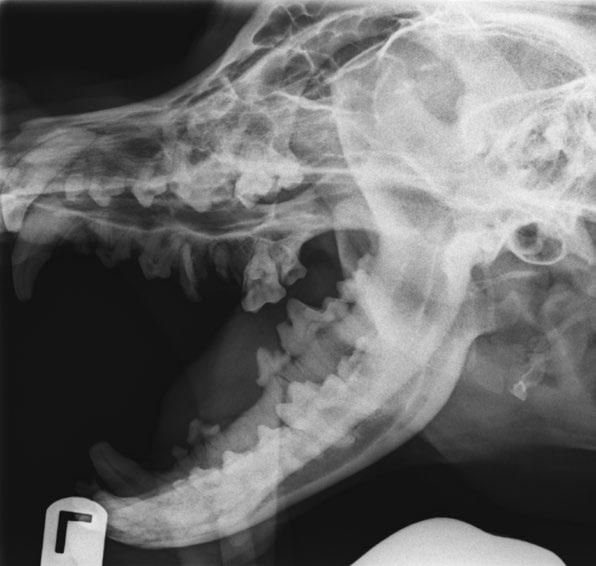

debemos hacer un buen diagnóstico y estadificación, ya que se trata de un tumor muy agresivo a nivel local que requiere un diagnóstico rápido y preciso y una extirpación quirúrgica adecuada a pesar de ser descrito como benigno. En el proceso diagnóstico del AAC se debe realizar un examen completo del paciente, estudio radiológico y, en aquellos casos que sea posible, el estudio complementario con TC para obtener más información acerca de su extensión (figura 1B). A nivel radiológico se observa una masa infiltrativa asociada al diente que causa desplazamiento dental y osteólisis variable, y que puede presentar mayor o menor apariencia quística (figura 2).

La principal diferencia del AAC con otros tumores odontogénicos es su capacidad de invadir hueso esponjoso, por lo que en radiología se observa infiltración ósea grave, desplazamiento dental e incluso reabsorción dental tanto a nivel local como a distancia. El mayor inconveniente de la evaluación radiográfica de estos tumores es la infravaloración de la extensión del hueso afectado, por lo que es conveniente realizar una tomografía computarizada para determinarla con mayor exactitud (Tjepkema, 2020).

La principal diferencia del AAC con otros tumores odontogénicos es su capacidad de invadir hueso esponjoso, por lo que en radiología se observa infiltración ósea grave, desplazamiento dental e incluso reabsorción dental tanto a nivel local como a distancia.

Técnica quirúrgica

La técnica va a depender de la localización del tumor. Estas lesiones se tratan mediante escisión en bloque con márgenes de al menos 1 cm. Según la experiencia de los autores, con márgenes de 2 cm siempre que sea posible, valorando tanto localización como tamaño del paciente, los resultados son óptimos.

Antes de realizar una mandibulectomía o maxilectomía parcial se deben tener en cuenta aspectos tales como:

la experiencia de los autores, para realizar la cirugía de forma más rápida y segura, mejorando los resultados y la recuperación del paciente.

El pronóstico para perros con AAC puede variar dependiendo de varios factores, incluido el tamaño, la ubicación, la extensión y la posibilidad de tratamiento. El diagnóstico precoz facilita que el pronóstico sea más favorable. Los perros que pueden ser tratados mediante cirugía en bloque con márgenes limpios suelen tener un pronóstico a largo plazo muy bueno. No obstante, en algunos casos se produce una recurrencia, por lo que las visitas periódicas de control y seguimiento son extremadamente importantes (Bolek, 2024).

• Maxilectomía rostral: escisión del hueso que rodea uno o más incisivos, incluyendo en caso de ser necesario uno o ambos caninos (figura 3).

• Maxilectomía central: escisión del hueso que rodea los premolares y/o molares y ocasionalmente un canino o ambos (figuras 4 y 5).

• Maxilectomía caudal: escisión del hueso que rodea los molares.